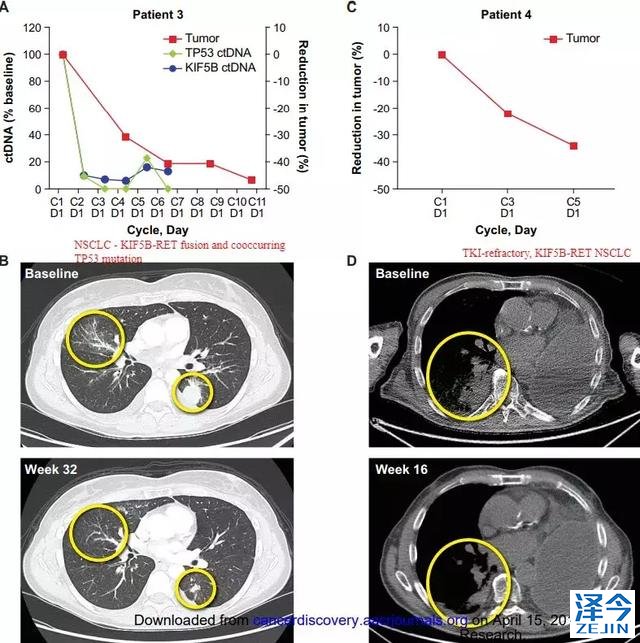

临床案例

1

72岁的汤姆卡特伊曾是空军飞行员。几十年来,他一直担任林务员,负责监督林地的地块。在他退休前的几年,一名护士在喉咙里发现了一个肿块。原来是甲状腺髓样癌(MTC),这是一种罕见且不可治愈的癌症。

化疗失败了的Cathey。他的医生将他送到MD安德森癌症中心,在那里他们有更多的MTC经验。他进入了包括免疫疗法Yervoy在内的临床试验。它只起效六个月,他的脖子和肝脏的肿瘤就又开始增长。

幸运的是,他进行了基因检测,RET阳性,他的医生建议他进入实验药物BLU-667的一期临床试验,BLU-667旨在比现有药物如Cometriq和Caprelsa更好地靶向该基因。

结果:他最大的肿瘤从6厘米缩小到了2厘米!他喜欢骑着自行车,从皮划艇上钓斑鳟,红鱼和近海鱼。

2

一位转移性NSCLC患者在接受治疗后“首次评估时脑部响应”。